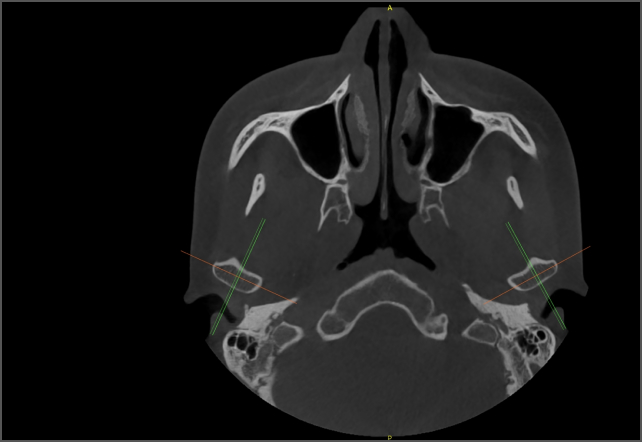

• CT閱片+正畸測(cè)量 CT閱片+正畸測(cè)量

無論是否有網(wǎng)絡(luò),都可在蘭臺(tái)醫(yī)令?影像中心上進(jìn)行CT閱片和正畸測(cè)量。多項(xiàng)AI圖像處理功能,讓醫(yī)生操作化繁為簡。

• lamtau AI TMJ

AI TMJ